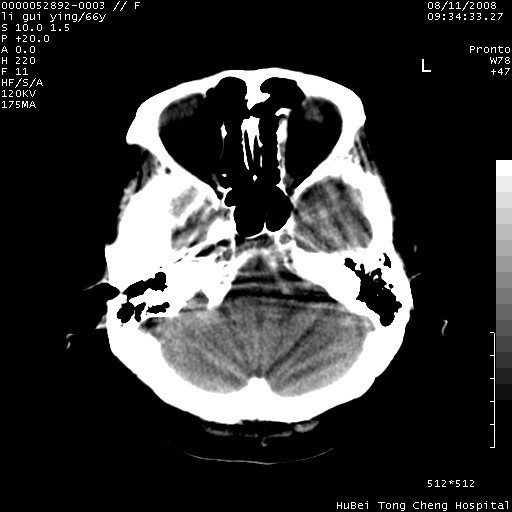

以下是引用yangyudong333在2008-8-12 12:22:00的发言:[br]1.病灶呈圆形[br]2.周围无水肿带[br]3.密度不均匀,内有点状钙化[br]4.无占位效应[br] 考虑良性占位性病变,血管瘤可能性大